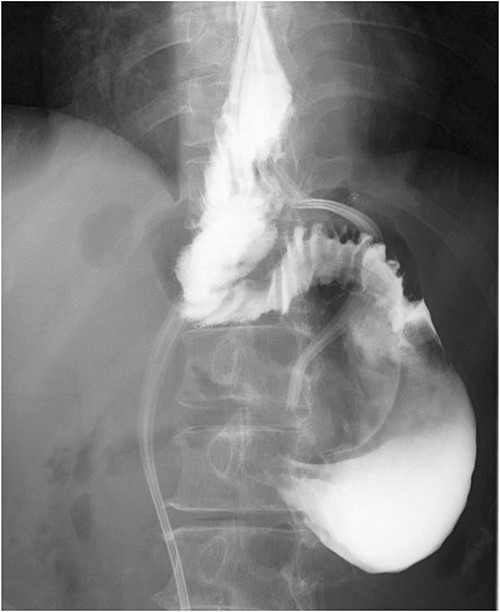

A 60-year-old female with dysphagia and vomiting visited the university hospital. In 2007, she underwent esophageal diverticulum resection (procedure unknown) with a diagnosis of an esophageal diverticulum, which subsequently recurred. In 2011, she underwent a transesophageal hiatus diverticulectomy and a fundoplication (Nissen procedure) at a local hospital. In 2013, dysphagia and vomiting appeared. The patient was diagnosed with recurrence and underwent balloon dilatation for follow-up. In 2015, the patient came to our hospital due to persistent symptoms. After one balloon dilation, the patient did not show any improvement and was referred for surgery. Esophageal fluoroscopy revealed a diverticulum 5 cm in size in the lower esophagus just above the eruption. There was no significant change in the diverticulum size before and after dilation (Figs 1 and 2). Gastrointestinal endoscopy revealed a diverticulum in the lower esophagus, with a residue accumulation (Fig. 3). The esophagus directly below the diverticulum was narrowed. The patient was diagnosed with recurrent lower esophageal diverticulum and underwent surgery.

Preoperative esophageal fluoroscopy (after dilation). There was no significant change compared to the pre-expansion period.